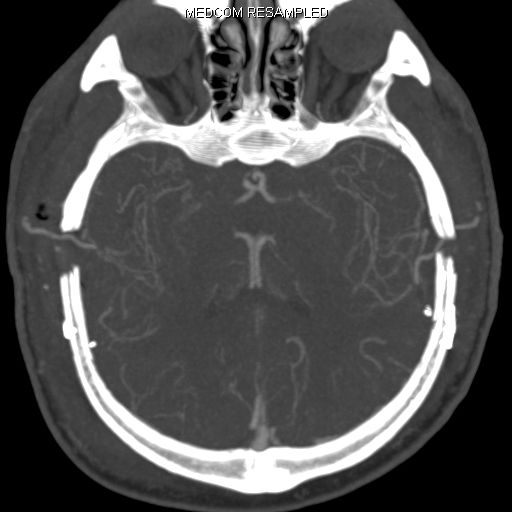

Die Krankheit tritt nur im Bereich der basalen Hirnarterien auf und dehnt sich nicht weiter auf die peripheren Hirngefäße aus. Da das Großhirn sechs Hauptversorgungsgebiete hat (jeweils beidseits eine vordere, eine mittlere und eine hintere Hirnarterie), können bei einer betroffenen Person bis zu 6 Gefäßterritorien betroffen sein. Welche Hirnareale definitiv beteiligt sind, kann man erst sicher nach der Durchführung einer Angiographie (Katheterdarstellung der Hirngefäße) sagen.

Angiografie einer Moymoya

Auf dem Bild mit einer Gefäßdarstellung “Angiographie” kann man die dünnen Kollateralen (Wolken-ähnliches Bild) um die Gefäßengstelle am Ende der inneren Halsschlagader erkennen.

Die konventionelle cerebrale Angiographie ist die wichtigste Untersuchung zur Diagnosestellung der Moyamoya Krankheit. Diese Untersuchung ist zu vergleichen mit einer Herzkatheteruntersuchung, eben nur mit Darstellung der Hirnarterien. Bei Moyamoya-Patientinnen und Patienten werden, im Gegensatz zu Routineuntersuchungen bei anderen cerebralen Erkrankungen, selektiv die vordere und hintere Zirkulation des Gehirns dargestellt, sowie auch die Versorgung der extrakranialen Gefäße. Diese umfassende Darstellung ist besonders wichtig, um die vollständige Ausdehnung der Erkrankung zu erfassen und alle möglicherweise veränderten Blutflüsse im Gehirn zu verstehen. Je nach Befund werden die Engstellen der Hirnarterien, sowie auch mögliche begleitende Veränderungen selektiv hochauflösend dreidimensional dargestellt. Es ist wichtig zu erwähnen, dass die Moyamoya Krankheit nicht über eine Katheterintervention (Ballonaufweitung der Engstelle) behandelt werden kann und darf. Dies haben mehrere Studien gezeigt.

Angiographie beidseitige Moyamoya Krankheit

Konventionelle Angiographie eines Patienten mit beidseitiger Moyamoya Krankheit (links). 3-dimensionale Darstellung eines Aneurysmas einer jahrelang stark beanspruchten Spontan-Kollaterale (rechts).